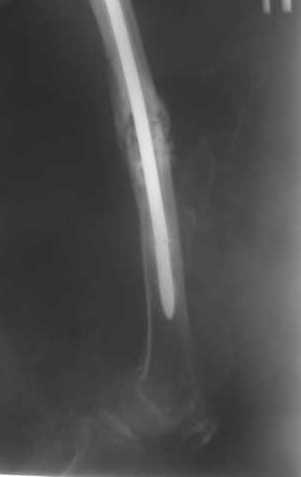

В приложении как раз видна эволюция использововшихся у нас большеберцовых гвоздей. Первый - дизайн как у UTN, второй - разнесены 45 градусные отверстия (зачем их вообще изначально так нелепо на одном уровне сделалм???), третий - убрано сиавшее лишним статическое отверстие, Herzog's bend перемещен более проксимально.